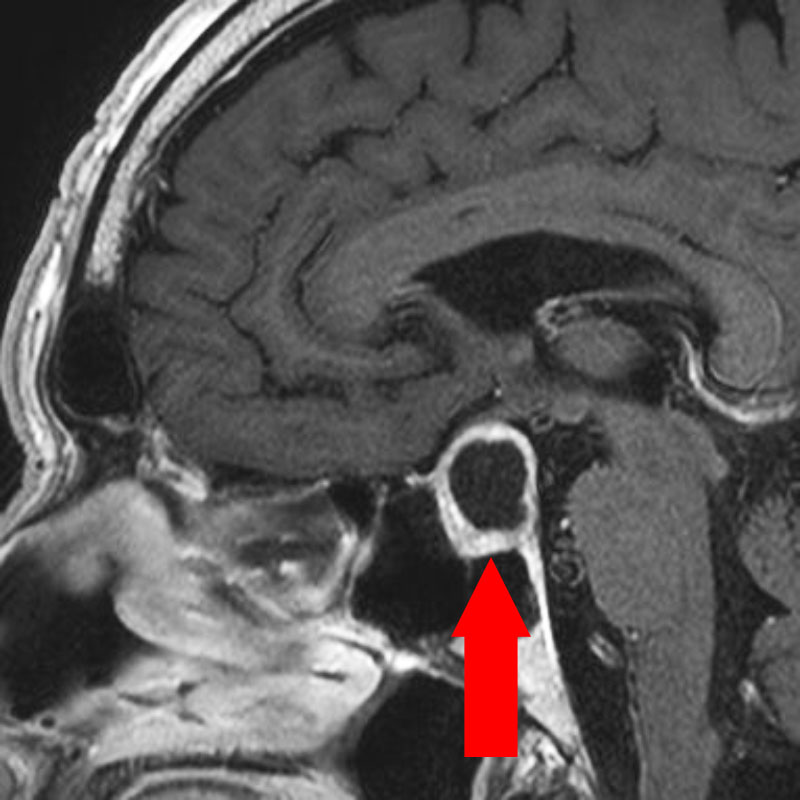

頭蓋内腫瘍摘出術

No.’23_52 手術前1

No.’23_52 手術前2

下垂体巨大腺腫